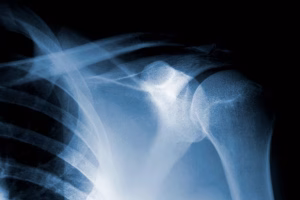

El dolor de hombro es una de las consultas más frecuentes en traumatología y rehabilitación. Entre las causas más comunes destacan la tendinitis calcificante y la bursitis subacromial, patologías que provocan dolor intenso, limitación del movimiento y dificultad para realizar tareas diarias como vestirse, cargar objetos o incluso dormir.

La tendinitis calcificante ocurre cuando se forman depósitos de calcio dentro de los tendones del manguito rotador. Estos depósitos generan inflamación, dolor intenso y restricción del movimiento.

La bursitis es la inflamación de la bursa, una pequeña bolsa llena de líquido que actúa como amortiguador entre los huesos y los tendones. En el hombro, la bursa subacromial se inflama debido a movimientos repetitivos, traumatismos o degeneración articular.